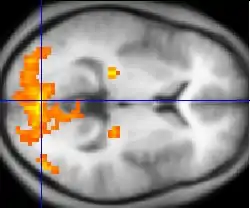

Changes in brain activity are closely coupled with changes in blood flow in those areas, and knowing this has proved useful in mapping brain functions in humans. The measurement of haemodynamic response, in a clinical setting, can be used to create images of the brain in which especially active and inactive regions are shown as distinct from one another. This can be a useful tool in diagnosing neural disease or in pre-surgical planning. Functional MRI and PET scan are the most common techniques that use haemodynamic response to map brain function. Physicians use these imaging techniques to examine the anatomy of the brain, to determine which specific parts of the brain are handling certain high order functions, to assess the effects of degenerative diseases, and even to plan surgical treatments of the brain.

Functional magnetic resonance imaging

Functional magnetic resonance imaging (fMRI), is the medical imaging technique used to measure the haemodynamic response of the brain in relation to the neural activities.[12] It is one of the most commonly used devices to measure brain functions and is relatively inexpensive to perform in a clinical setting. The onset of neural activity leads to a systematic series of physiological changes in the local network of blood vessels that include changes in the cerebral blood volume per unit of brain tissue (CBV), changes in the rate of cerebral blood flow, and changes in the concentration of oxyhemoglobin and deoxyhemoglobin. There are different fMRI techniques that can pick up a functional signal corresponding to changes in each of the previously mentioned components of the haemodynamic response. The most common functional imaging signal is the blood-oxygen-level dependent signal (BOLD), which primarily corresponds to the concentration of deoxyhemoglobin.[13] The BOLD effect is based on the fact that when neuronal activity is increased in one part of the brain, there is also an increased amount of cerebral blood flow to that area which is the basis of haemodynamic response. This increase in blood flow produces an increase in the ratio of oxygenated hemoglobin relative to deoxygenated hemoglobin in that specific area. The difference in magnetic properties of oxygenated and deoxygenated hemoglobin is what allows fMRI imaging to produce an effective map of which neurons are active and which are not. In short, deoxygenated hemoglobin is paramagnetic while oxygenated hemoglobin is diamagnetic. Diamagnetic blood (oxyhemoglobin) interferes with the magnetic resonance (MR) signal less and this leads to an improved MR signal in that area of increased neuronal activity. However, Paramagnetic blood (deoxyhemoglobin) makes the local magnetic field inhomogenous. This has the effect of dephasing the signal emitted in this domain, causing destructive interference in the observed MR signal. Therefore, greater amounts of deoxyhemoglobin lead to less signal. Neuronal activity ultimately leads to an increase in local MR signaling corresponding to a decrease in the concentration of deoxyhemoglobin.[14]

If fMRI can be used to detect the regular flow of blood in a healthy brain, it can also be used to detect the problems with a brain that has undergone degenerative diseases. Functional MRI, using haemodynamic response, can help assess the effects of stroke and other degenerative diseases such as Alzheimer's disease on brain function. Another way fMRI could be used is in the planning of surgery of the brain. Surgeons can use fMRI to detect blood flow of the most active areas of the brain and the areas involved in critical functions like thought, speech, movement, etc. In this way, brain procedures are less dangerous because there is a brain mapping that shows which areas are vital to a person's life. Haemodynamic response is vital to fMRI and clinical use because through the study of blood flow we are able to examine the anatomy of the brain and effectively plan out procedures of the brain and link together the causes of degenerative brain disease.[15]